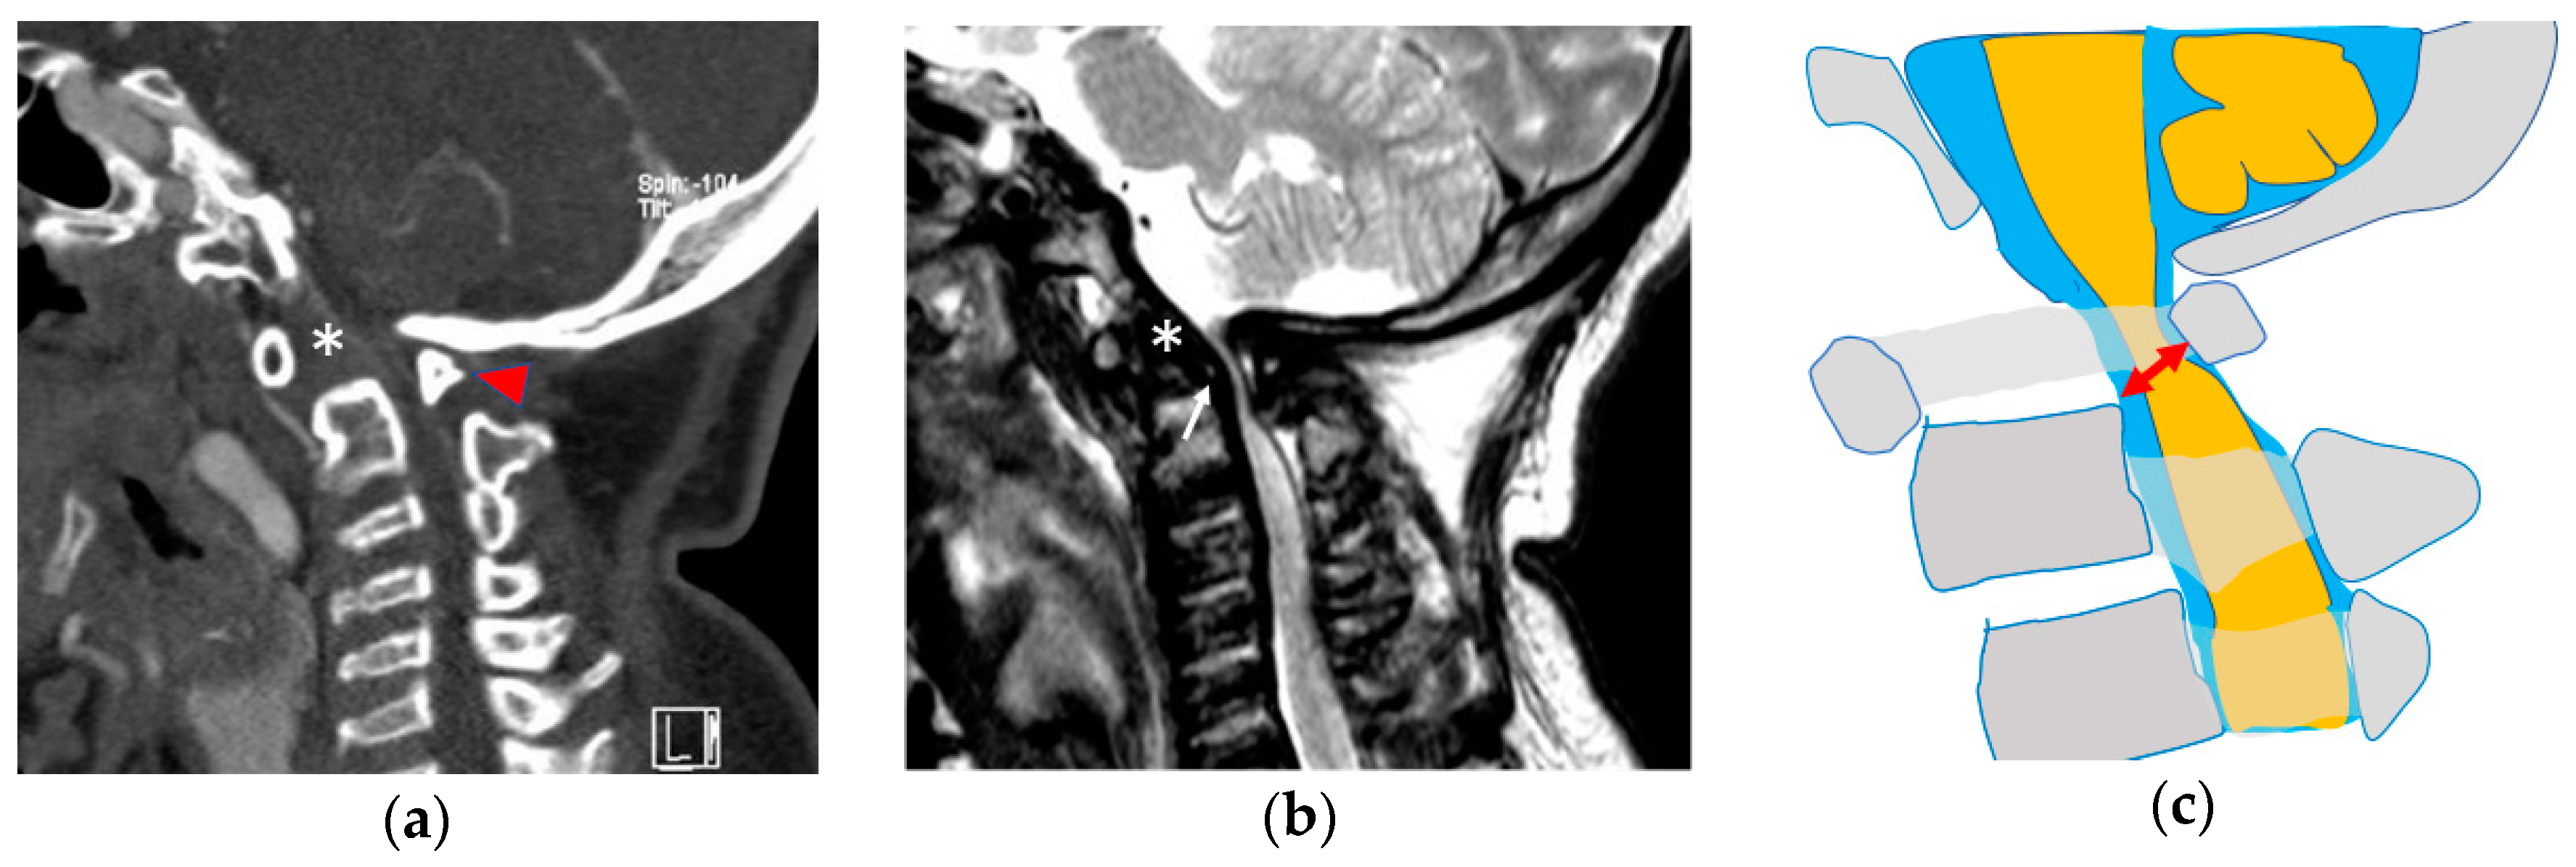

Figure 2.

Atlantoaxial instability in MPS IVa. Hypoplasia of the dens (asterisk) and C1 posterior arch (arrowhead) are more clearly recognized in computed tomography (a), while GAG accumulation (white arrow) and spinal cord compression are more identifiable in magnetic resonance images (b). The space available for the cord (red arrow) indicates the most narrowing between the posterior wall of C2 and the C1 posterior arch (c). This patient had tetraplegia and required ventilator control because of irreversible spinal cord damage at the craniocervical junction.